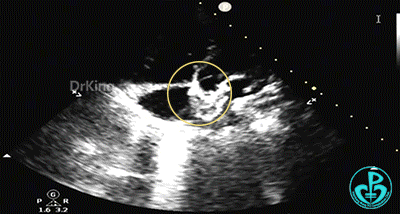

左盘展开

左盘展开,牵拉成型线,使左盘面成型。

右盘展开

右盘展开,牵拉成型线使得封堵器双盘扣合住间隔。

锁定前确认

牵拉试验,封堵器骑跨于缺损两侧。

封堵器整体稳定,仅右盘随钢缆牵拉移动。